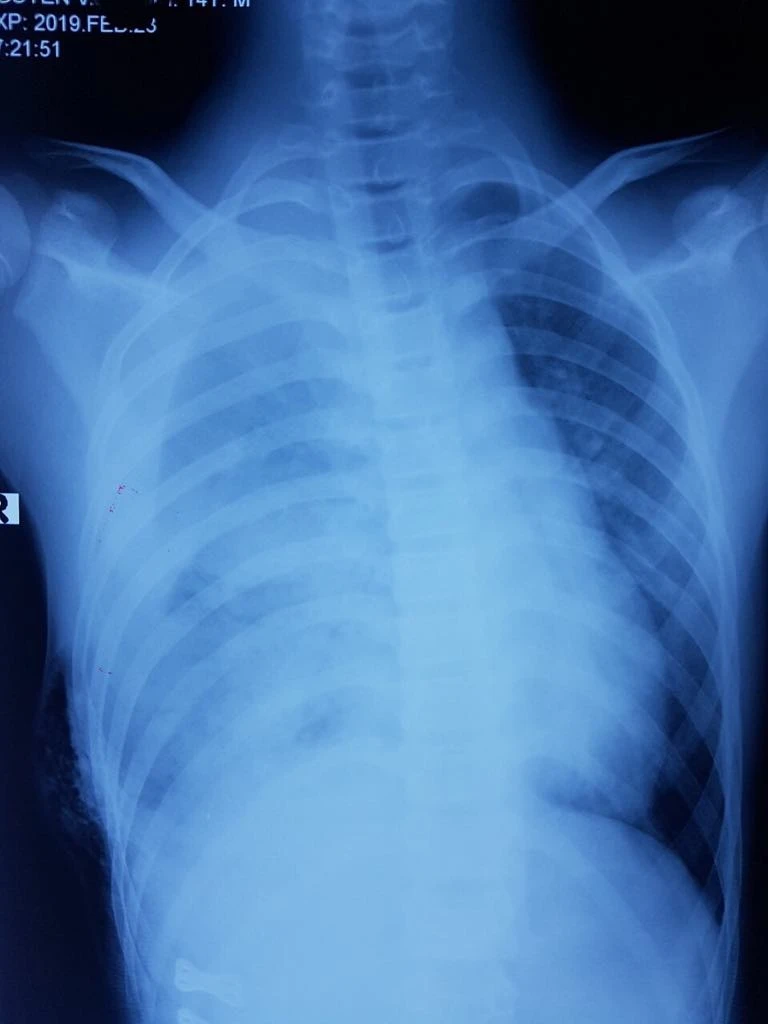

Phim chụp X-quang của bé U. Ảnh: BVCC

Tại đây, bé được ghi nhận bị cọc sắt có chiều dài ước tính 10-20cm xuyên từ bụng tới ngực phải, mất nhiều máu dọa sốc, đa chấn thương nặng, huyết áp tụt, tràn máu màng phổi nhiều làm xẹp hết một bên phổi gây suy hô hấp nặng nề.

Bé U. đã được Ban lãnh đạo BV và kíp trực tổ chức hội chẩn liên khoa, khẩn trương cấp cứu, đồng thời cho làm các xét nghiệm. Kết quả siêu âm, X-quang cho thấy bệnh nhi bị đa vết thương, rách cơ hoành, vỡ gan, tràn máu phổi phải lượng nhiều. Êkip gồm hơn 10 y bác sĩ đã khẩn trương vừa hồi sức tích cực vừa tiến hành phẫu thuật cho bệnh nhi. Ca phẫu thuật kéo dài 5 giờ 30 phút đã giành lại sự sống cho bé U.